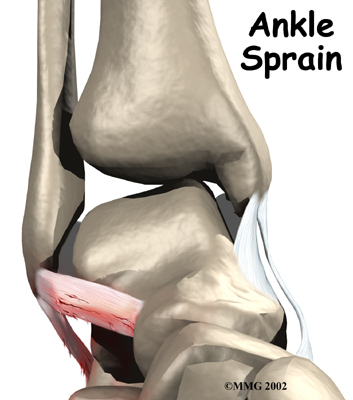

Ankle Sprain and Instability

An ankle sprain is a common injury and usually results when the ankle is twisted, or turned in (inverted). The term sprain signifies injury to the soft tissues, usually the ligaments, of the ankle.